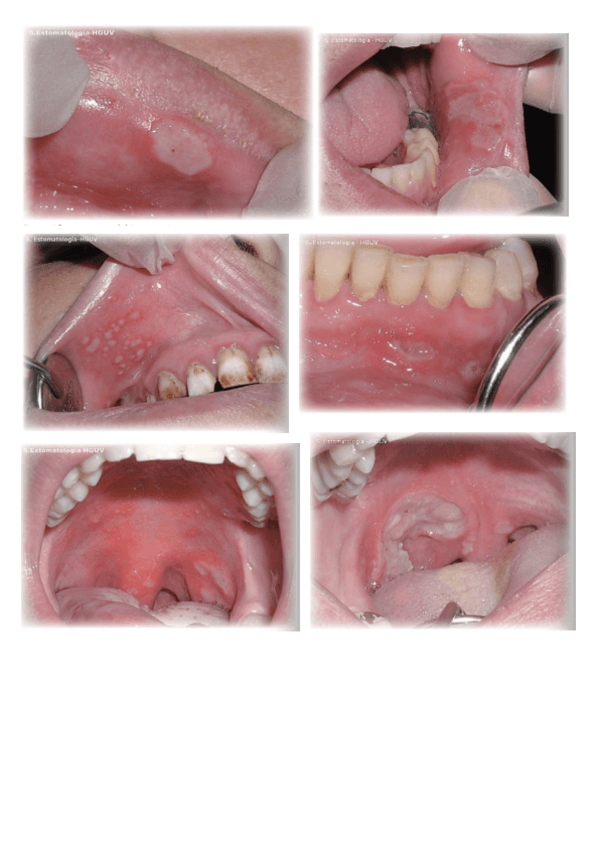

Imagenes-Practicas.pdf